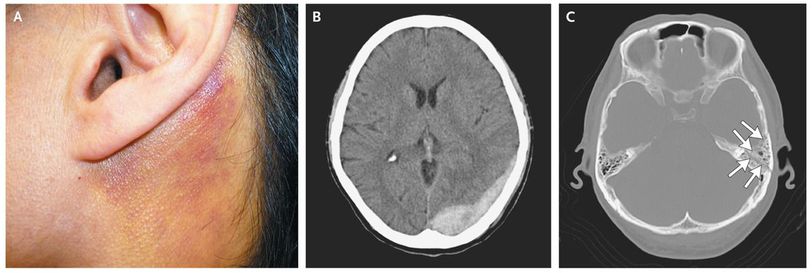

A 46-year-old man presented to the otolaryngology clinic with hearing loss and a sensation of fullness in the left ear. The symptoms had started a few days before presentation. He had no other neurologic symptoms. Otoscopy revealed a hemotympanum through the eardrum. In addition, a subcutaneous hemorrhage was observed in the left postauricular region (Panel A). The patient reported no history of head injury but said that he had been having partial memory blackouts since drinking alcohol at a New Year's party 5 days earlier. Computed tomography revealed an acute epidural hematoma (Panel B), accompanied by a left temporal bone fracture (Panel C, arrows). The patient was sent to the neurosurgery department for evaluation, where it was determined that no intervention was required. The patient's symptoms improved over the next several weeks, with the exception of slight sensorineural hearing loss in the left ear, detected on audiometry. Battle's sign represents ecchymosis around the mastoid process from head trauma that has caused a temporal bone fracture. The sign can suggest that a patient has sustained a significant blow to the skull, even if the medical history is obscure.